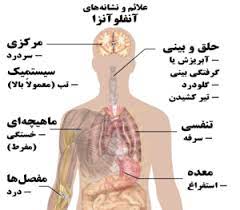

قیمت: 58٬000 تومان - دسته بندی فایل: علوم پزشکیپاورپوینت آنفولانزا

فروش ویژه پاورپوینت حرفه ای آنفولانزا با تخفیف استثنائی ... دسته بندی: پاورپوینت نوع فایل (.ppt) PowerPoint (قابل ویرایش و آماده پرینت) تعداد اسلاید :75 اسلاید

قیمت: 48٬000 تومان - دسته بندی فایل: علوم پزشکیپاورپوینت آشنایی با بیماری آنفولانزا(Influenza)

فروش ویژه پاورپوینت حرفه ای آشنایی با بیماری آنفولانزا(Influenza) با تخفیف استثنایی فقط 49 هزار تومان 39 اسلاید